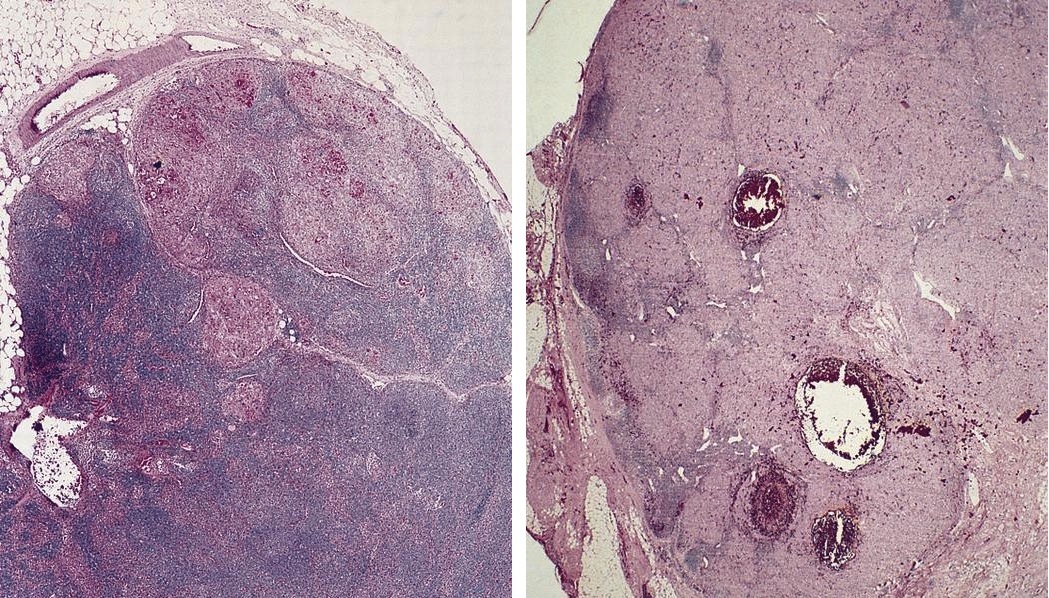

Microscopic (histologic) images

AFIP images

- Post vaccination bacille Calmette-Guerin infection occurs in 1% of infants, although swelling usually subsides (Braz J Med Biol Res 2004;37:697)BACILLARY ANGIOMATOSIS Left: Proliferated blood vessels are separated by abundant eosinophilic, vaguely fibrillary material. Some neutrophils are also seen. Right: Barely canalized blood vessels separated by eosinophilic interstitial materials in the absence of neutrophils.